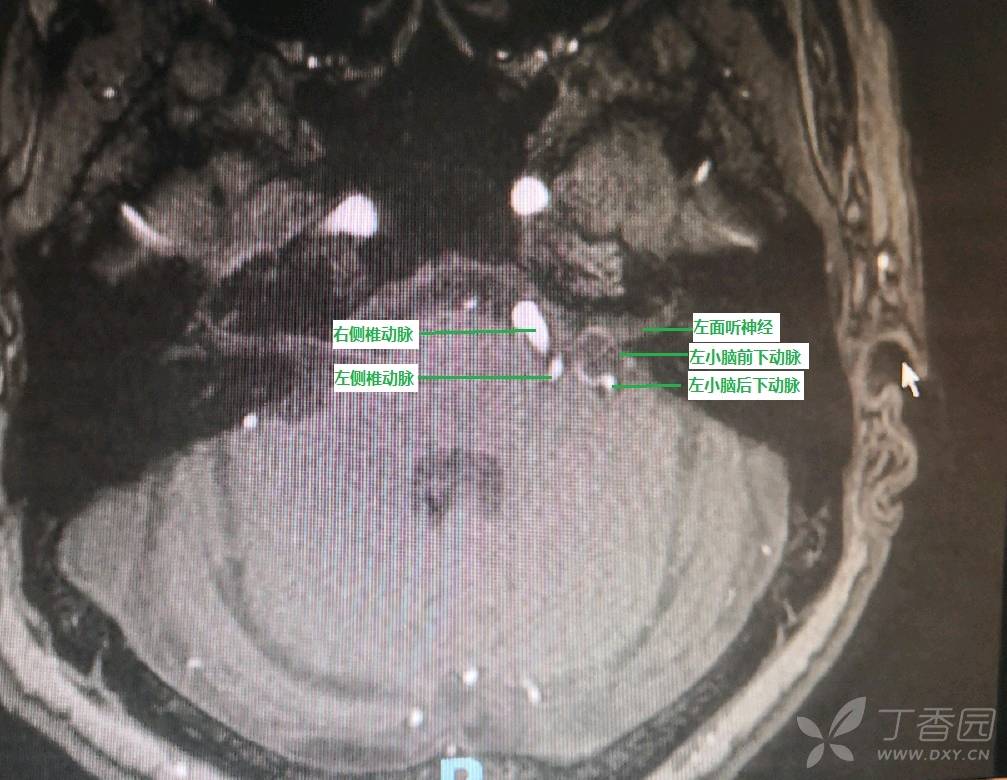

女性,69岁,主因“左侧面颊部不自主抽搐2年,加重半年”入院,诊断为左侧面肌痉挛。查体发现左侧面颊部不自主抽动,余查体无特殊。既往体健。入院行三叉神经/面神经 3.0T MRI检查发现左侧面神经受多条血管压迫(见图1)

图1 头MRI提示左侧面神经与双侧椎基底动脉、左侧小脑前下动脉、左小脑后下动脉位置关系毗邻